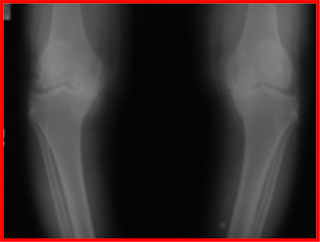

ภาพเอกซเรย์แสดงการสึกกร่อนของข้อเข่าทำให้กระดูกมาชิดกันมากขึ้น